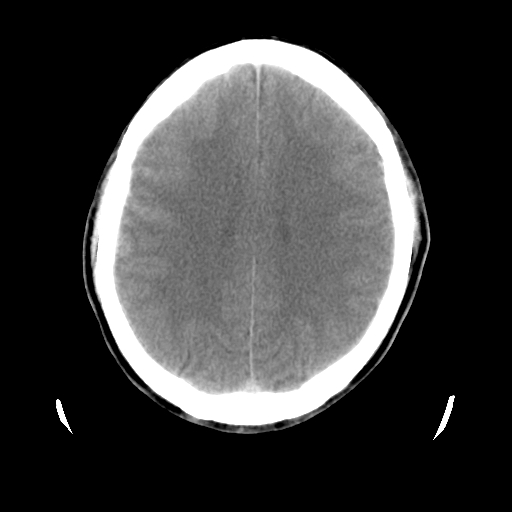

男,51岁,头外伤一小时,呕吐两次。

1)左侧中颅窝蝶骨翼后方硬膜外血肿。2)左侧颞顶部硬膜下血肿。3)蛛网膜下腔出血。4)左侧筛窦及双侧蝶窦炎症(或积血)。5)左侧额部头皮软组织肿胀。